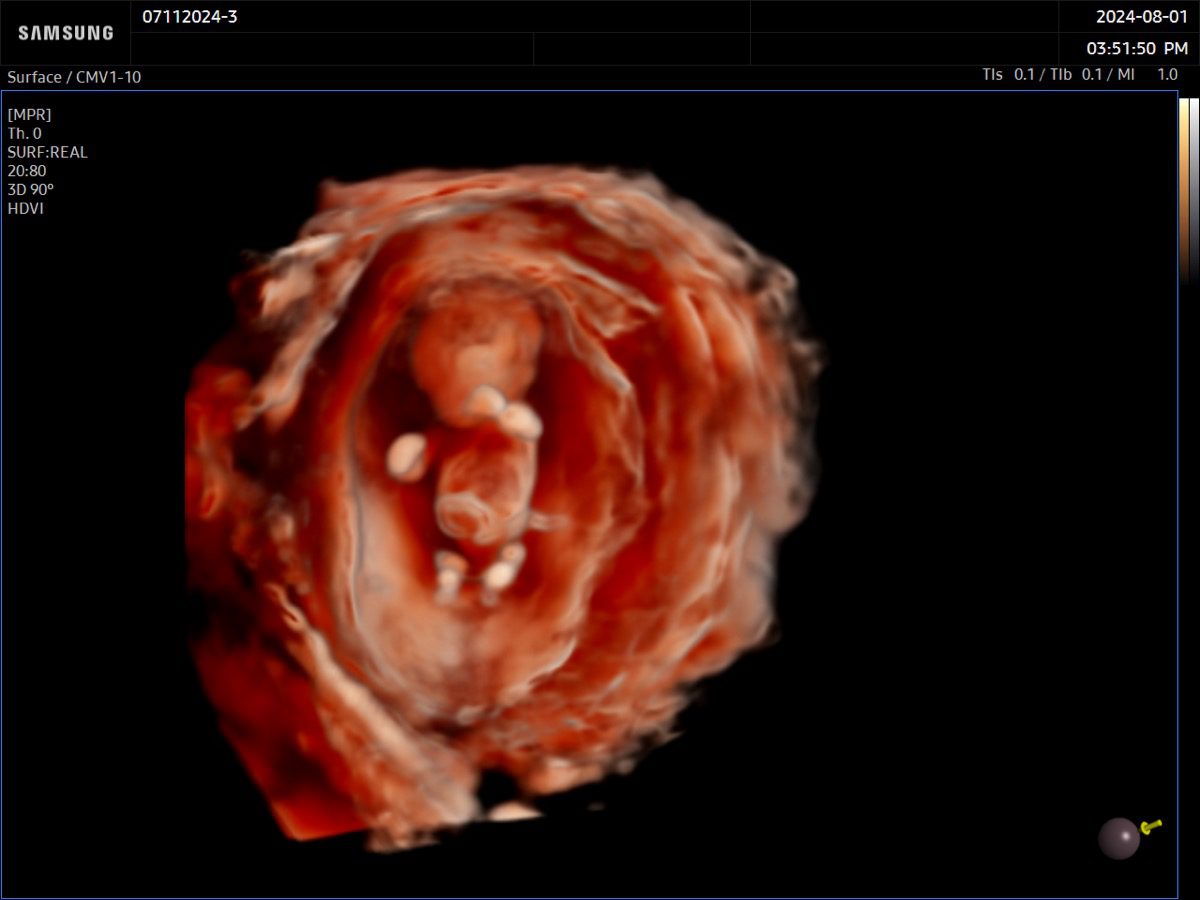

Comprehensive, advanced and expert MFM care for high-risk pregnancies

- Multiple births

- Fetal anomalies